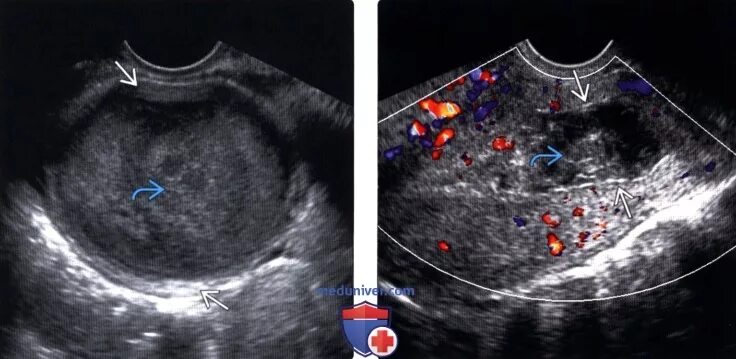

Гематометра симптомы